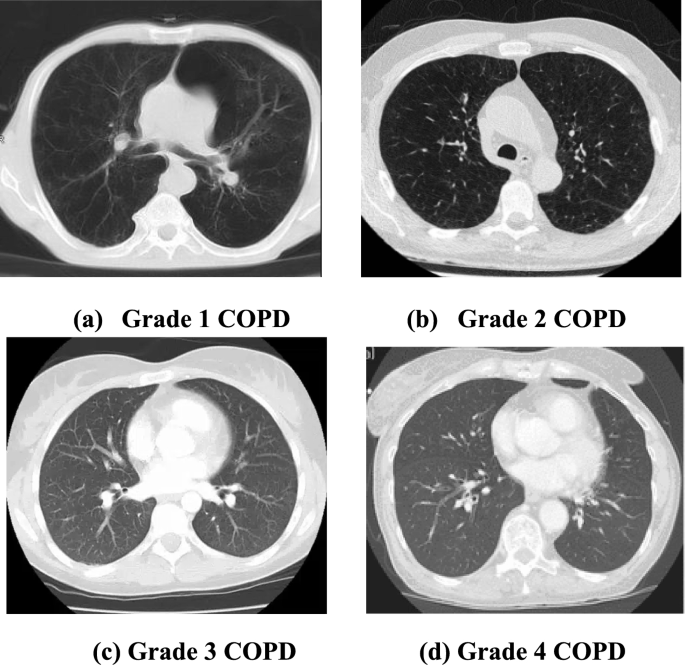

Hence there arises a huge need for an automated system that identifies and classifies the various stages of COPD depending upon the severity. Also, the economic burden that the disease places on its patients is exceedingly high and is estimated to be around 6% of the European Union’s financial budget annually. It is a heterogeneous disease that involves numerous smaller respiratory disorders. It is usually caused by the continuous exposure of the air tract and the lungs to micro particles that is often toxic and allergic4. It has four distinct stages classified by the Global initiative for chronic Obstructive Lung Disease (GOLD) such as stage 1, stage 2, stage 3, and stage 4. While the first stage is considered to be mild and the second one moderate, stages 3 and 4 are considered to be severe and very severe in nature. As the disease progresses, symptoms such as breathlessness, cough, dyspnea, and exacerbations intensify5. Although many imaging modalities such as magnetic resonance imaging, ultrasound and computed tomography images are available, specialists believe that the CT images of the affected lungs will function as the proper base for the identification of COPD. Various other signals such as electromyography signals, sounds of breathing etc. can also be used for identifying the disease. By identifying the disease in earlier stages, we can prevent the disease from progressing to further stages and also reduce the costs associated to the treatment.

The proposed system is implemented within the environment of python including pre-defined libraries of TensorFlow and Keras. 560 self-acquired CT lung images were divided in the ratio 80:20 for KELM classifier training. 448 images are used for training the classifier and 112 images for evaluating it. For grade 1 COPD, 104 images were used to train the classifier, and 30 images were used for testing. For grade 2 COPD, 113 images were utilized for training and 25 for testing. Similarly for grade 3 and 4, 131 and 157 images were employed in total. The details of dataset division are given in Table 1 below.

Figure 5 shows the sample CT images of patient’s lungs affected by COPD.